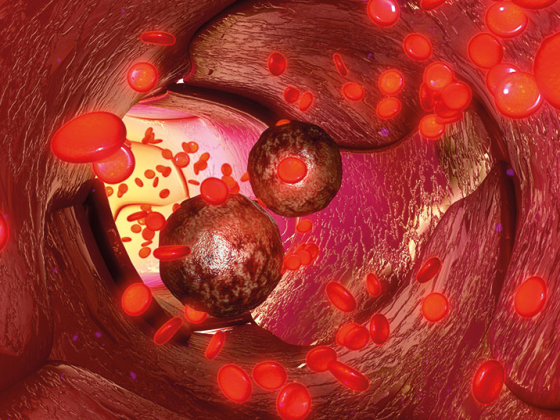

Bentracimab ist ein neuartiges, rekombinantes, humanes monoklonales Antikörper-Antigen-bindendes Fragment, das die thrombozytenaggregationshemmende Wirkung von Ticagrelor bei schweren Blutungen und dringenden chirurgischen Eingriffen aufheben soll. Alfasigma hat nun die europäische Lizenz für Bentracimab von PhaseBio erworben.